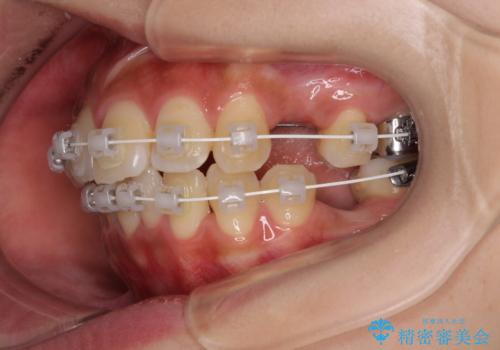

アンカースクリューと補助装置を使用して上顎大臼歯を遠心移動させることで咬み合わせを改善し、更には口元の突出感を改善するために上下左右の小臼歯4本を抜歯し、ワイヤー装置によりデコボコを解消しながら口元の突出感も改善していくこととしました。

上下の前歯が接触する仕上がりとなったので、横顔の印象が大幅に改善されました。